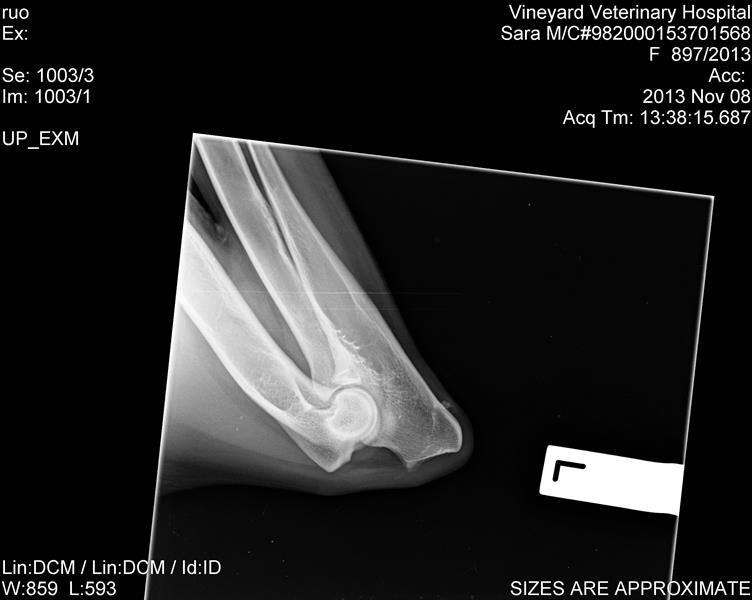

I had some feedback from someone i emailed with the scans, they look pretty good, was the comment.

"Her hips and elbows are fairly good. The hips - the right hip is just slightly shallow and just slightly loose - nothing to worry about, the left hip has a very slight thickening of the cranial acetabular edge, again nothing to worry about, her elbows are normal. There is a calcinosis ( calcium deposit next to one elbow - again not an issue, won't cause any lameness etc.

Her hips would probably score around 6-8 on the right and 4-5 on the left. The pass mark for the "A" stamp is a maximum of 8 points in total with no more than 3 points in any one area. Certainly would not be concerned about either of her hips or elbows as a long term issue,"